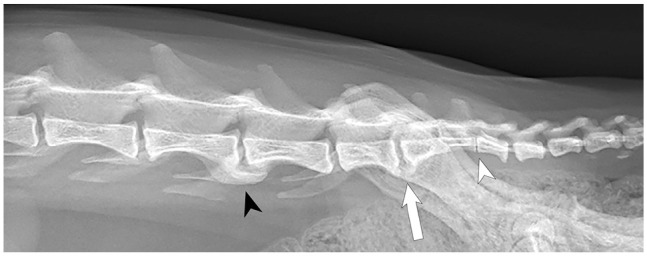

Case summary: A 10-year-old female spayed domestic shorthair cat was evaluated for a 6-week history of abnormal tail carriage and constipation. Examination revealed tail paresis and pain over the lumbosacral and sacrocaudal articulations and on tail manipulation. MRI revealed a contrast-enhancing mass within the vertebral canal over the lumbosacral disc space, compressing the cauda equina. The mass filled the epidural space, resulting in complete attenuation of the cerebrospinal fluid signal. Laminectomy and durotomy were performed over L7-S1, revealing white, firm material within the subarachnoid space. Microscopically, the material was consistent with degenerative intervertebral disc material. Postoperatively, the clinical signs resolved completely.

Relevance and novel information: Intervertebral disc herniation (IVDH) is uncommon in cats, with most cases involving extradural compression of nervous tissue. Reports describing intramedullary intervertebral disc extrusions in cats are rare. To the authors' knowledge, the present case is the first reported intradural-extramedullary intervertebral disc extrusion in a cat. Although MRI can often delineate extradural lesions, it can be insensitive in differentiating intradural-extramedullary from intramedullary lesions. In the present case, the location of the lesion within the vertebral canal at the lumbosacral disc space made the determination of the lesion's location with respect to the meninges challenging. Moreover, the strong contrast enhancement of the lesion raised an index of suspicion for neoplasia. Surgical intervention and histopathology confirmed an intradural-extramedullary IVDH. The present case adds to a growing body of literature regarding IVDH in cats and details the imaging findings of intradural-extramedullary IVDH in a cat.